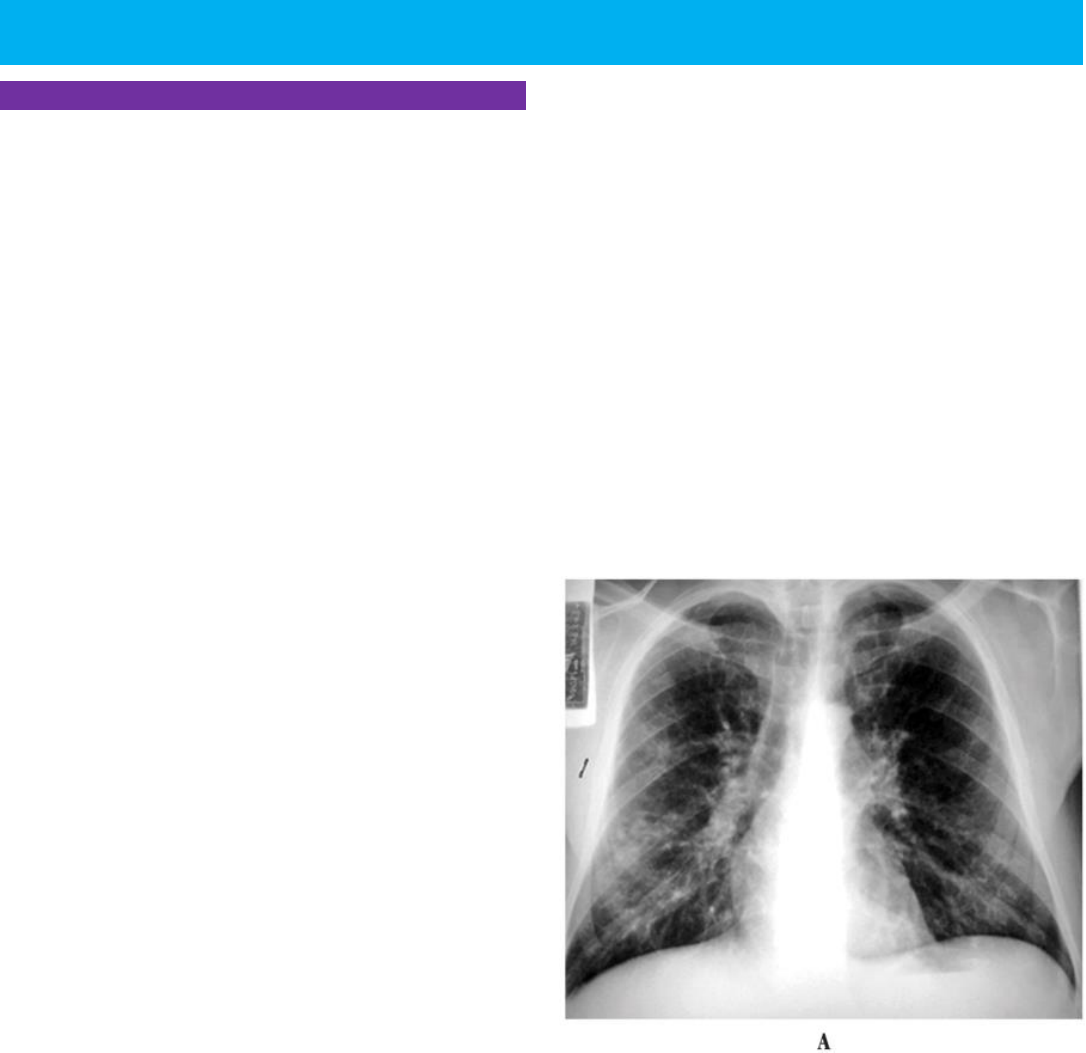

O Raio-X desses pacientes irá aparecer como um infiltrado

bilateral que acomete praticamente todo os pulmões, em

especial as regiões da base, sendo como se pintasse todo

o pulmão com tinta branca, de maneira intersticial. Esse é

uma característica que difere da tuberculose, que afeta na

maioria dos casos as regiões apicais dos pulmões, já nesses

casos de Pneumocistose afeta menos as regiões do ápice.

Nesses casos não ocorre a presença de adenomegalia hilar

que é o aparecimento de regiões edematosas onde se tem

a origem dos pulmões com os linfonodos aumentados nos

locais e também não se apresenta derrame pleural nesses

casos. Lembrando que a tuberculose é o principal tipo de

diagnostico diferencial nesses casos, se assemelhando as

vezes no quadro clínico, e se não for possível diferenciar os

dois quadros, deve-se realizar o tratamento para ambos e

em casos que o paciente chega muito grave.